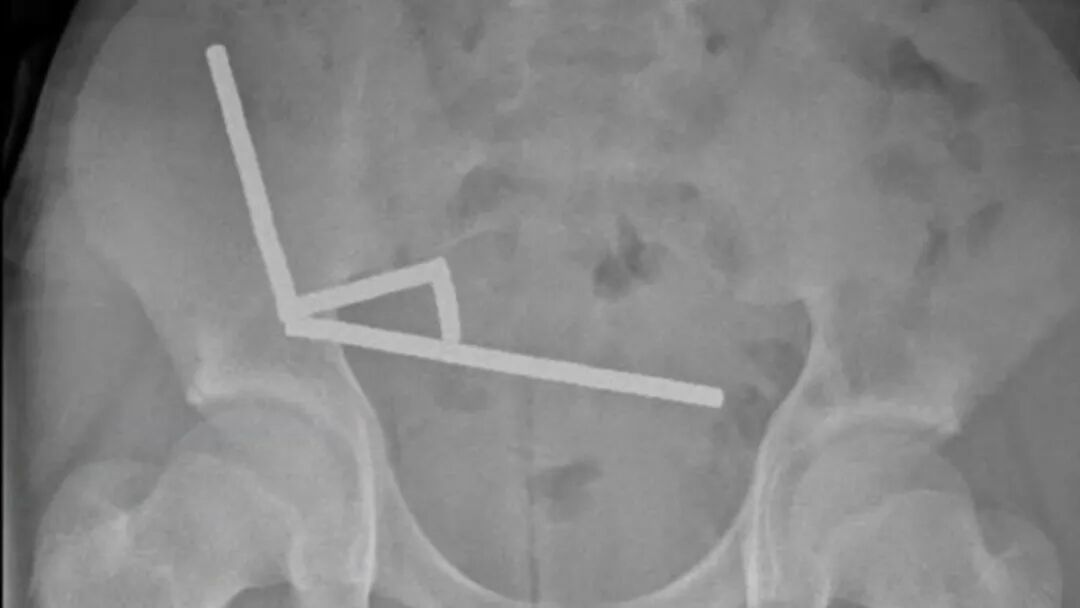

一位13岁的新西兰男孩因为腹部疼痛到医院就诊。在X光片检查中,医生发现他的下腹部出现了由几根笔直“线条”构成的诡异图案。

男孩的腹部X光片 | Lekamalage et al., NZMJ, 2025

这些“线条”的真面目是将近200块强磁铁,男孩承认,自己在大约一周前把它们吞进了肚子。互相吸引的磁铁狠狠地挤压着男孩的肠道,已经造成多处组织坏死。在去除磁铁时,医生不得不将坏死的肠道一并切除[1]。